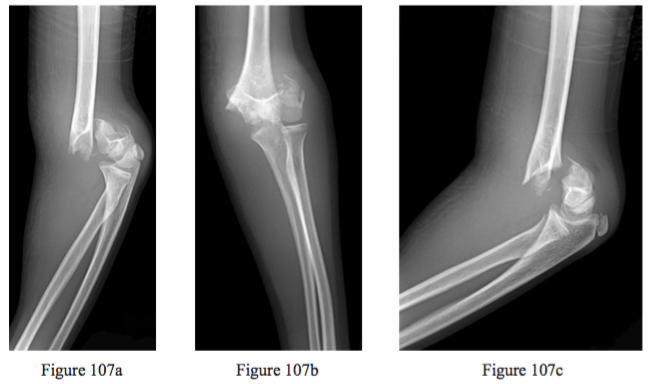

Question 107

Figures 107a through 107c are the radiographs of a 9-year-old girl who is seen in the emergency department 1 hour after a fall from monkey bars. A gross deformity is noted at the left elbow, but there are no lacerations or open areas in the skin. She is further assessed and found to have delayed capillary re ll, diminished radial artery pulsation in the ipsilateral hand, and decreased ability to ex her ngers and wrist (when compared to the contralateral side). What is the best next step?